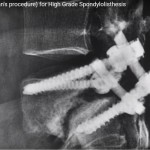

Bohlmann Procedure(Trans Sacral Fibula) for High Grade Spondylolisthesis

Courtesy: Dr Kshitij Chaudhury, Dr Kshitij Chaudhary is a fellowship-trained spine surgeon working at Sir HN Reliance Foundation Hospital Mumbai, India. He has been trained in USA at Harvard University’s Beth Israel Medical Center, Boston and Twin Cities Spine Center, Minneapolis. Web: http://spinemumbai.in/